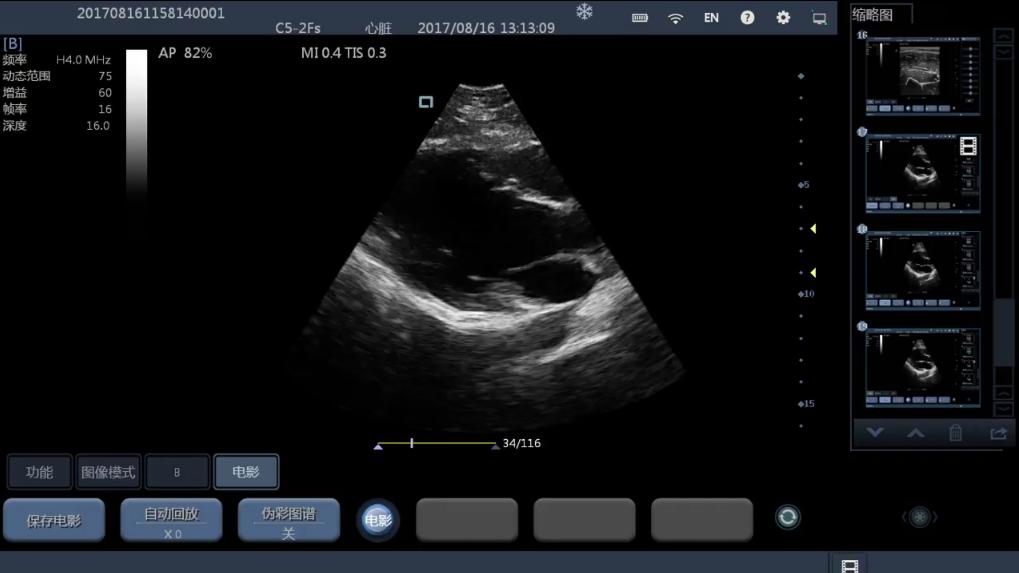

Esto es lo que le ofrecemos con el ecógrafo D8 . Un transductor de solo 220 gr al que podemos cambiar los cabezales y que se conecta a cualquier teléfono, tableta con sistema operativo ANDROID o iOs u ordenador Windows que tenga una conexión WIFI y que dispone de los modos de imagen B, B-M, C, P, PW.

Hay 2 versiones disponibles actualmente cuya única diferencia es el tipo de imagen que presenta, una únicamente con imagen en Blanco/negro y otra con Doppler color, Power y PW.

El objetivo del sistema es disponer de imagen de calidad (128 elementos) para poder detectar derrames pericárdicos, líquido torácico o hemorragia interna en la sala de emergencias o en la ambulancia, lo que permite el inicio inmediato del tratamiento ; Ver el feto a medida que crece ; Detectar los latidos cardíacos fetales ; Controlar la cantidad de líquido amniótico durante el parto ; Encontrar placa en la carótida para evitar el accidente cerebrovascular antes de que suceda ; Colocar líneas en las venas con ayuda visual ; Encontrar nódulos en tiroides, hígado o senos durante la exploración ; Monitorear cálculos en los riñones, vesículas biliares y vejigas ; Verificar fracturas óseas sin rayos X ; Determinar el nivel de lesión muscular; Ver marcadores en quirófano, etc.

C5-2Ks Convex 2-5 Mhz Radio 50 Abdomen, Obstetricia, Urologia, etc

Pulse en las imágenes para ver a mayor tamaño.